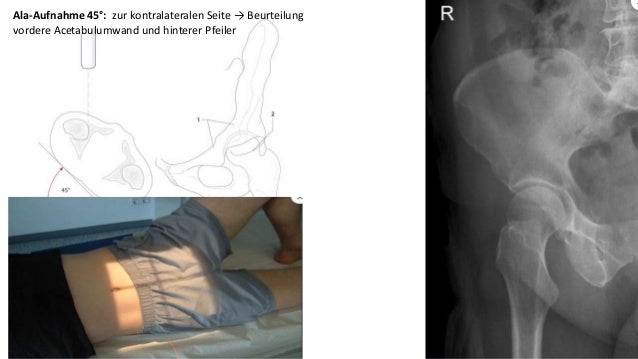

Spezielle Roentgen Aufnahmeb Unfallchirurgie

Source: slideshare.net

spezielle unfallchirurgie roentgen.